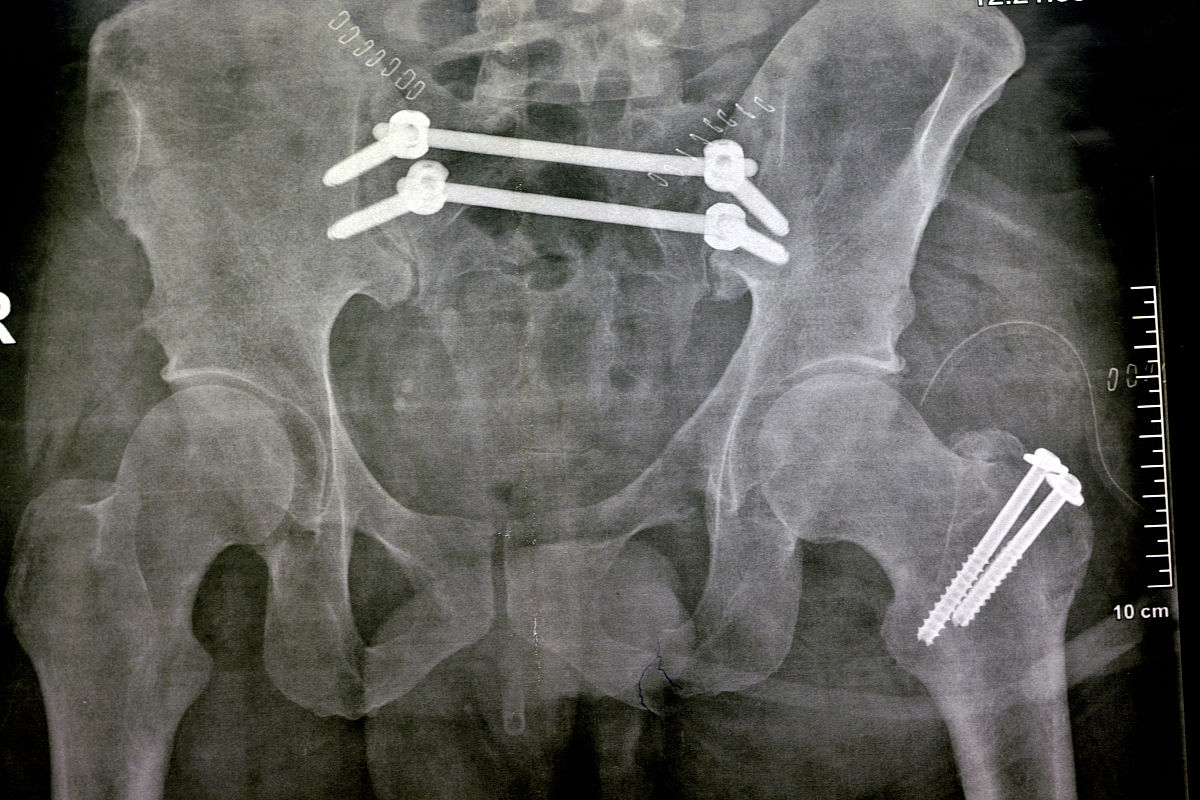

股骨颈骨折合并骨盆骨折:全髋关节置换术后心理护理指南

股骨颈骨折合并骨盆骨折患者接受全髋关节置换术后,积极的心理状态对康复至关重要。以下护理建议旨在帮助患者平稳度过术后恢复期: